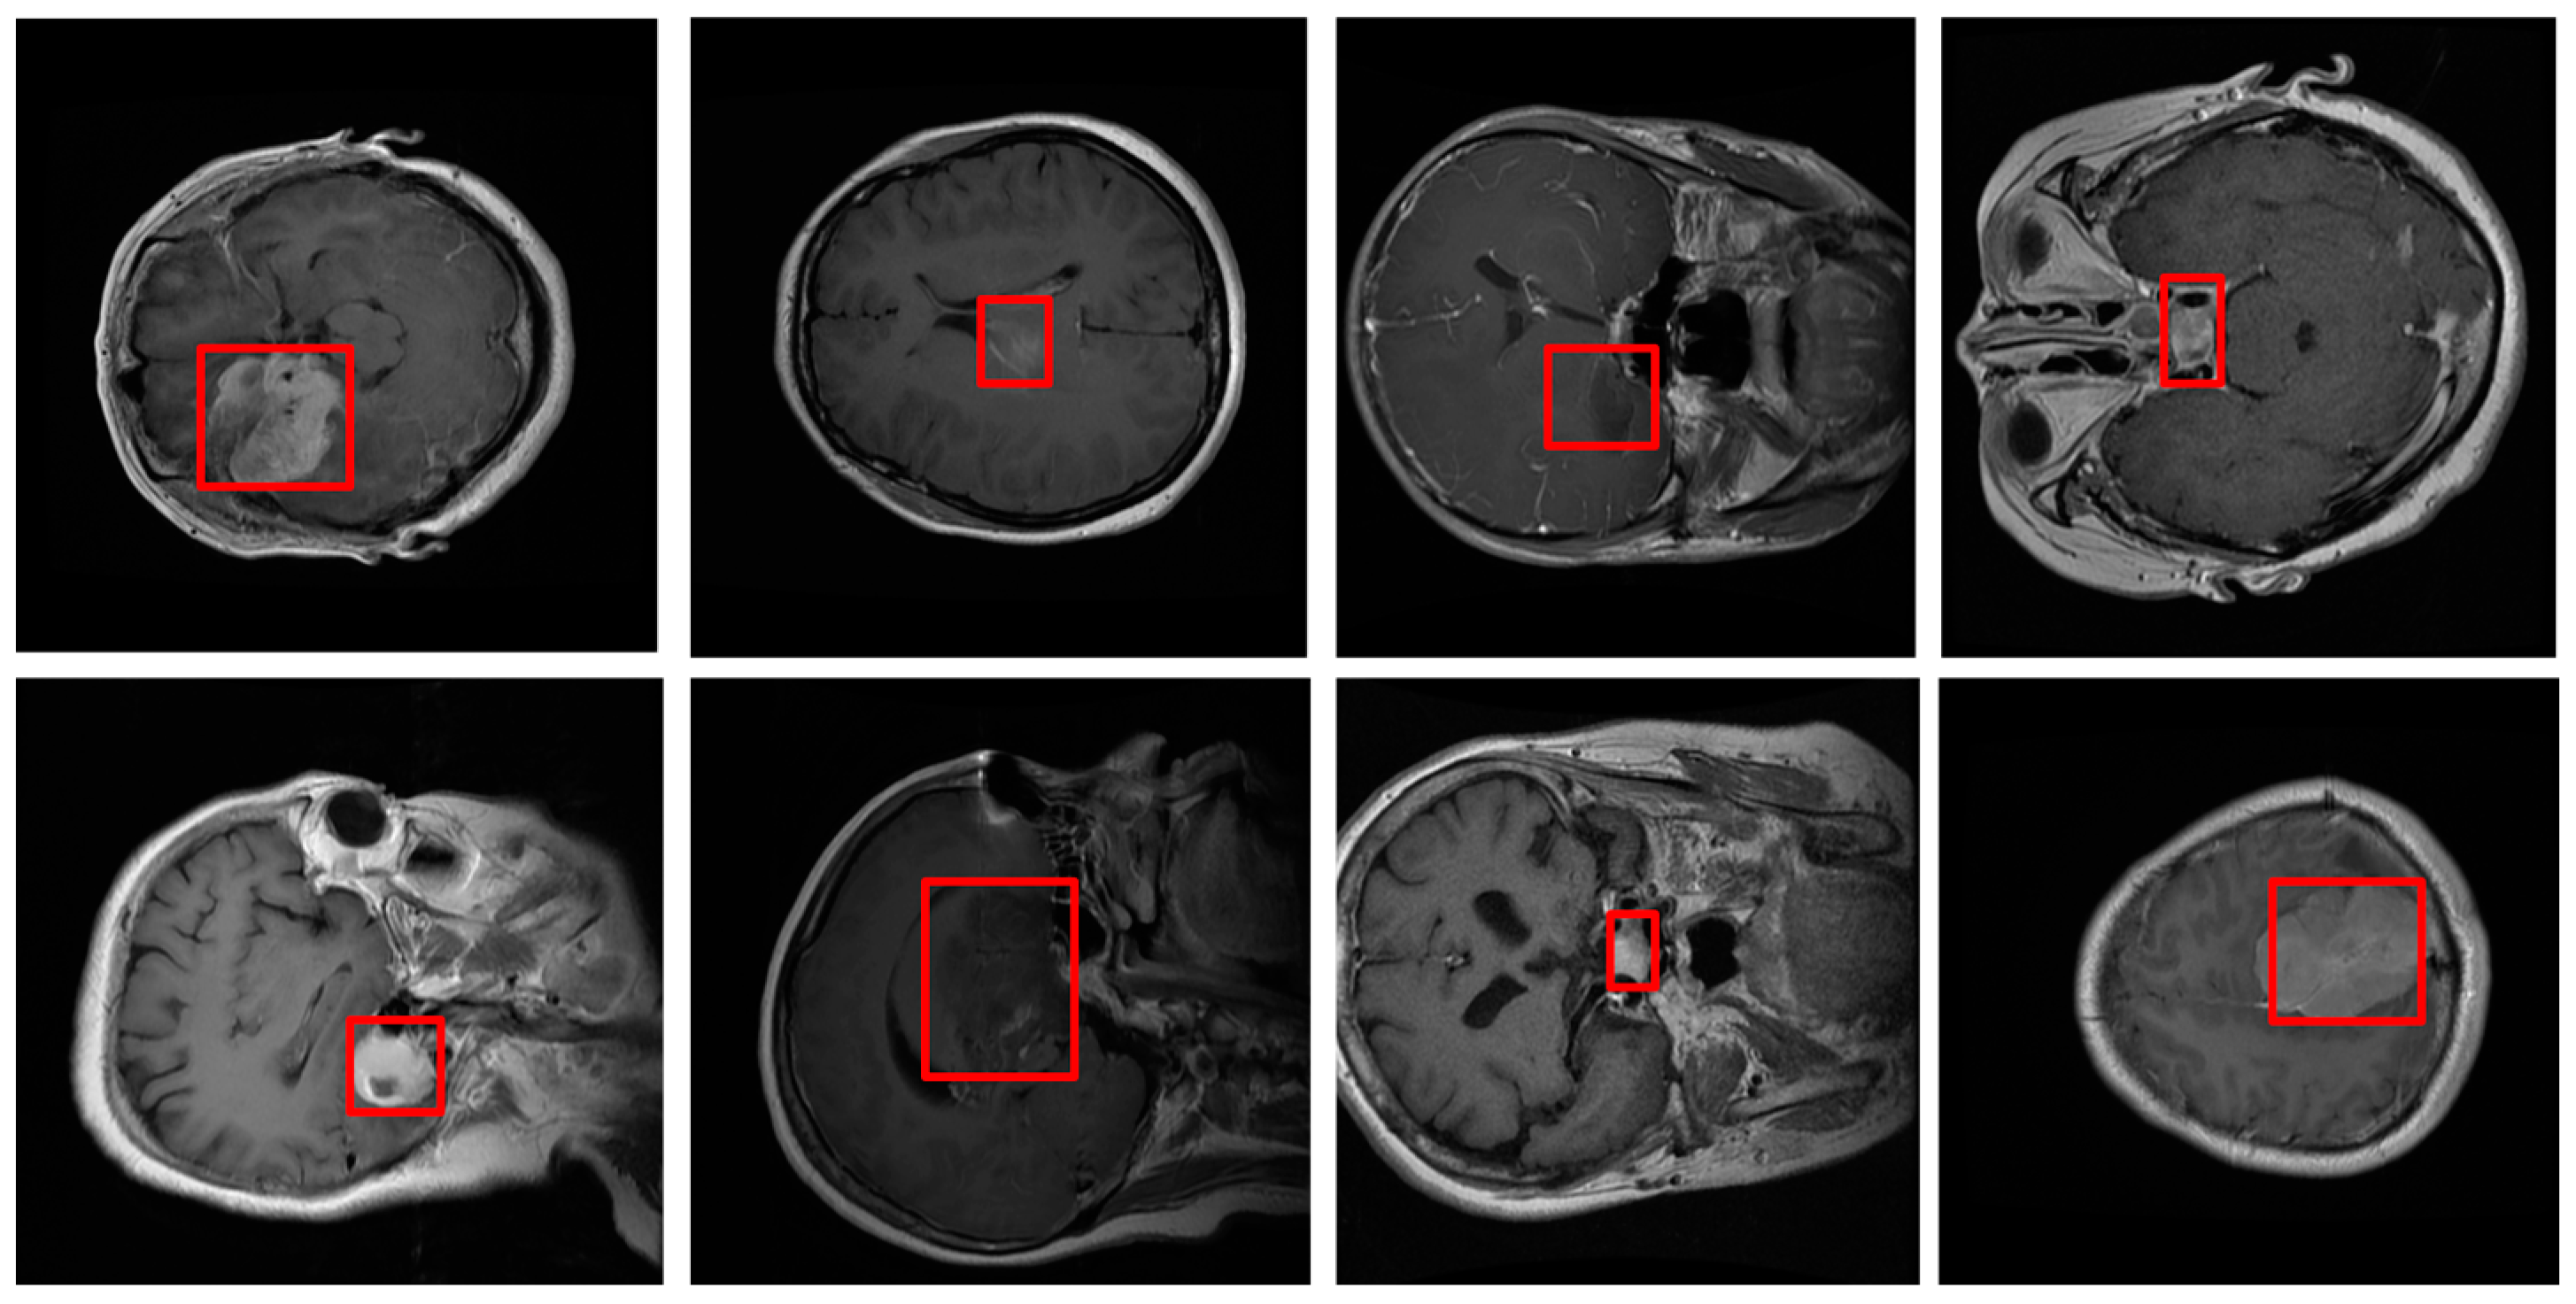

- Our model was evaluated on the Figshare dataset, which includes annotated MRI images of different brain tumor types: meningioma, glioma, and pituitary tumors. We provide a comprehensive comparison against leading segmentation models. Our results demonstrate that the proposed model achieves superior performance across metrics like accuracy, DSC, precision, and recall, confirming its robustness and reliability for clinical application.

4.1. The Dataset